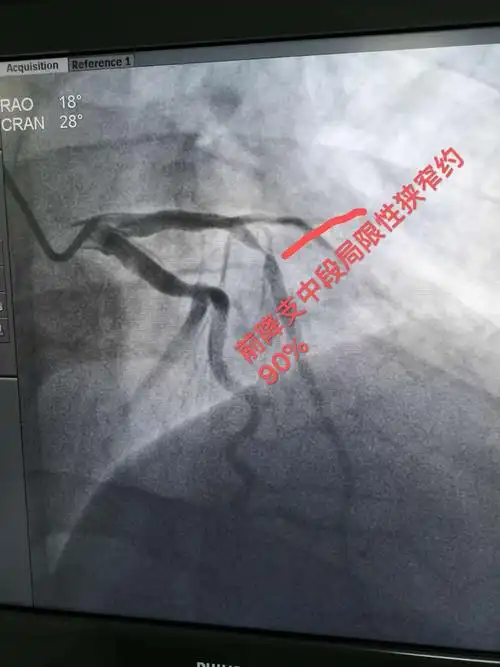

冠状动脉造影示前降支中段局限性狭窄约90%